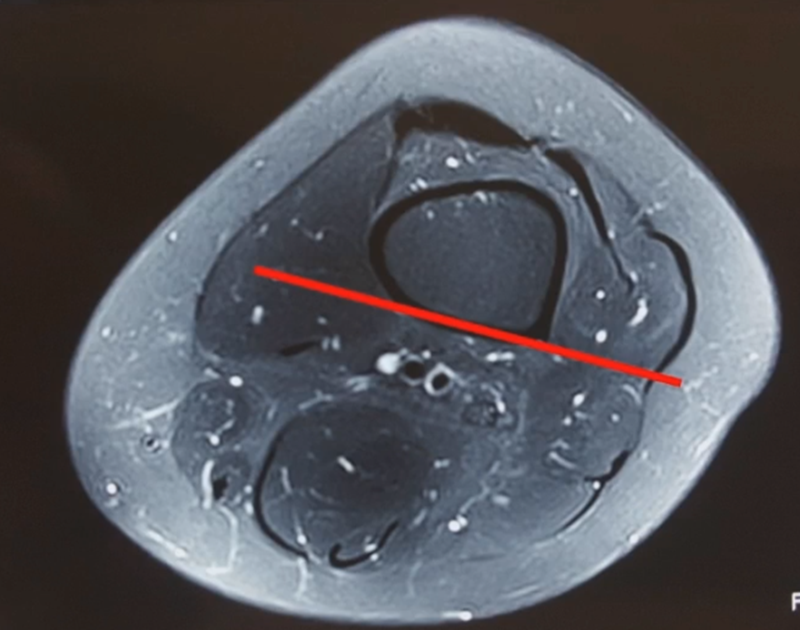

影像学检查显示左侧出现合页断裂。

进行翻修,术前力线显示内翻。